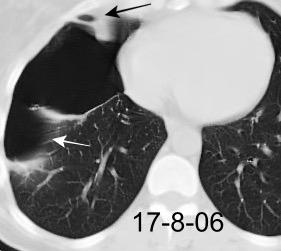

Marzo 2014: Perforación longitudinal distal secundaria a episodio de vómito (síndrome de Boerhaave). Derrame pleural izdo. que evoluciona a empiema.

Wang C-T et al. Tension hydropneumothorax in a Boerhaave syndrome patient: A case report . World J Emerg Med, 2021. Katabathina V et al. Nonvascular, nontraumatic mediastinal emergencies in adults:a comprehensive review of imaging findings. Radiographics. 2011.